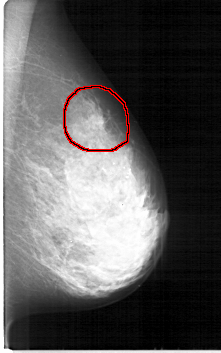

D_4114_1.LEFT_MLO

LEFT_MLO LINES 5281 PIXELS_PER_LINE 3301 BITS_PER_PIXEL 12 RESOLUTION 43.5 OVERLAY

FILE: D_4114_1.LEFT_MLO.OVERLAY

TOTAL_ABNORMALITIES 1

ABNORMALITY 1

LESION_TYPE MASS SHAPE IRREGULAR MARGINS ILL_DEFINED

ASSESSMENT 3

SUBTLETY 4

PATHOLOGY MALIGNANT

TOTAL_OUTLINES 1

BOUNDARY